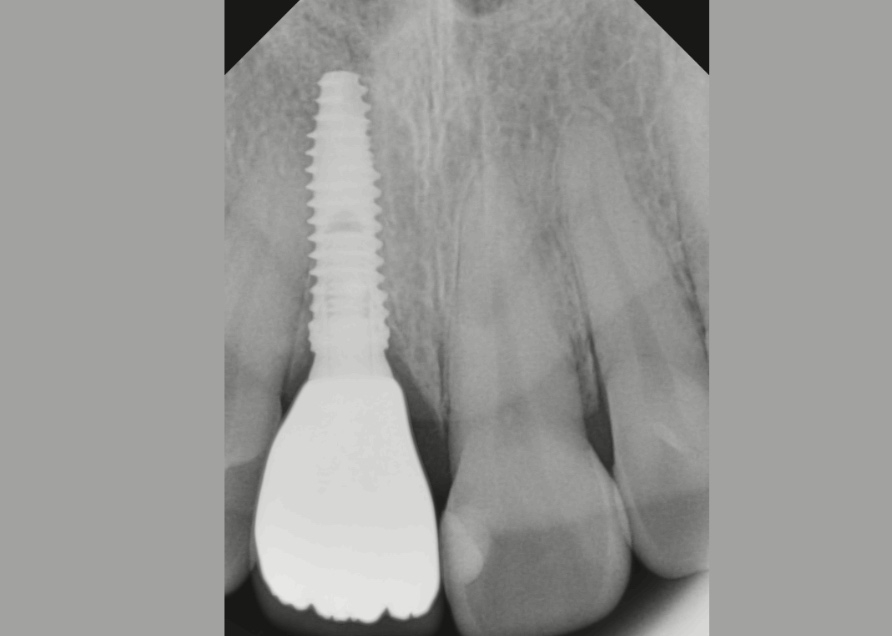

Одномоментно – имплант устанавливают сразу после удаления разрушенного корня в одно посещение;

Через 2-3 месяца – имплантацию проводят после заживления раны и восстановления костной ткани;

В отдаленный период времени – когда удаление зуба было давно.

Рекомендуемый срок установки импланта после потери зуба - 3-6 месяцев. Больший период выжидать мы не советуем, если пройдет больше времени, то могут возникнуть проблемы: атрофия костной ткани, и для того чтобы установить имплант понадобятся дополнительные процедуры (наращивание костной ткани и т.д.)